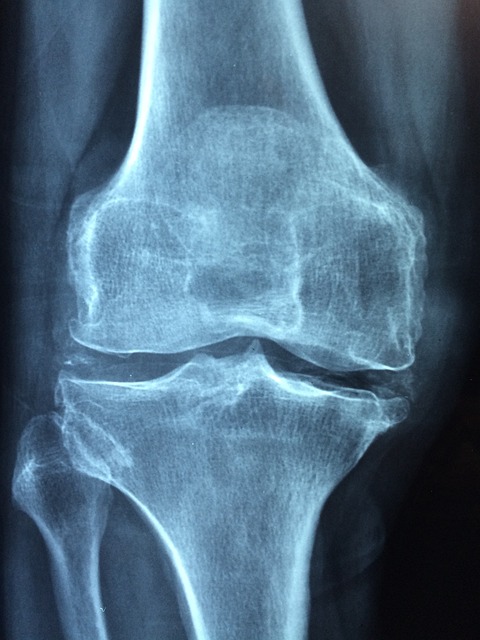

골다공증 예방과 치료에서 가장 중요한 영양소 중 하나는 단연 칼슘입니다. 칼슘은 뼈의 주성분으로, 적절한 섭취가 이루어지지 않으면 뼈가 약해지고 골밀도가 감소하여 골절 위험이 증가하게 됩니다. 이를 보충하기 위해 많은 이들이 칼슘제를 복용하거나 식사를 통해 칼슘을 섭취하고 있습니다.

칼슘 섭취의 궁극적인 목표는 뼈 건강 유지와 골다공증 예방입니다. 이를 실현하기 위해서는 단순히 칼슘만 섭취한다고 해서 충분하지 않으며, 흡수와 활용을 도와주는 다양한 요소들이 함께 작용해야 합니다. 이 점에서 식품 섭취 방식은 다양한 미량 영양소와 함께 칼슘을 공급하므로 전체적인 뼈 건강 유지에 더 효과적일 수 있습니다. 특히 비타민 K, 마그네슘, 인, 단백질 등도 함께 섭취되는 경우가 많아, 칼슘의 작용을 더욱 돕습니다.